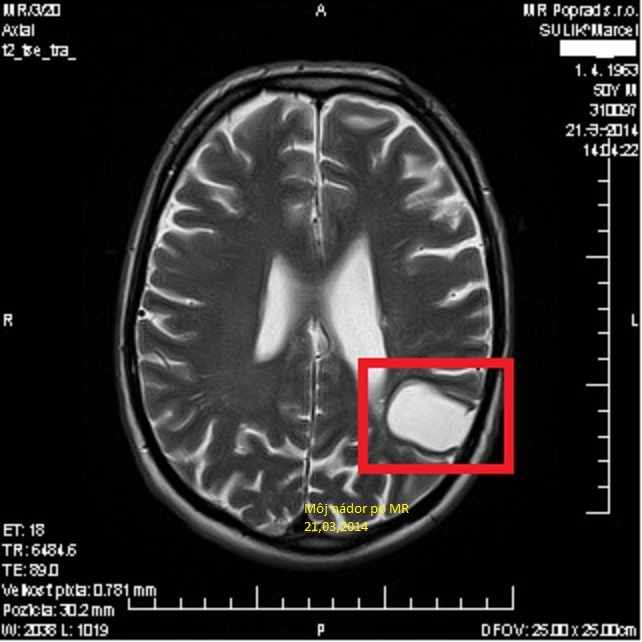

Prosím o finančnú pomoc na splatenie dlhov ktoré mi spôsobila zlá sociálna situácia. Som onkologický pacient, nemôžem pracovať, čo vyplýva s mojich lekárskych správ viď prílohy. Moje posledné vyšetrenie magnetickou rezonanciou zo dňa 21.03.2014 jasne zobrazuje zbytkovy nález nádoru na mozgu o veľkosti 2,4cm x2,6cm x3,6cm viď ďalšie fotografie v tejto výzve. No napriek tomuto všetkému mi Soc. poisť. prv znížila invalidný dôchodok na polovičný v sume 125€ z ktorého som mal vyžiť. Takto sa to naše krásne Slovensko stará o onkologických pacientov. Mám 51 rokov, no také niečo sa môže stať iba v tomto štáte, kde sa dosadzujú ľudia na posty, kde sa rozhoduje o prežití človeka s onkologickým ochorením. Bývam sám v 160ročnom dome. Dvakrát som sa odvolal na Krajský súd v Prešove kde som aj uspel no nebolo mi to nič platne, síce Soc. poisť. mi po viac ako roku a pol vrátila plný invalidný dôchodok no už v úplne inej výške, ako som poberal predtým. Spomínaný dlh som si spôsobil sám lebo som nevedel vyžiť zo 125€ mesačne. Pre upresnenie teraz poberám invalidný dôchodok vo výške 256€ no z neho musím splacať dlh vo výške 130€ mesačne, platím výživné na syna 50€ , 60€ inkaso- elektrina, plyn, vodné a stočne. a zase som na dne, neostáva mi ani na stravu lieky, a bežne poptreby. Viem že nie som sám s takýmto osudom, prosím so slzami v očiach dobrých ľudí pomôžte mi PROSÍM. Neviem čo viac o sebe napísať. Vopred ďakujem všetkým dobrým ľudom ktorý mi pomôžu prežiť.

I am asking, for financial assistance to pay off my debts which caused me a bad social situation. I am a cancer patient who is not able to work, as can be seen with my medical reports, see attached file. My latest MRI scan dated 21.3.2014 clearly shows the residual finding of a brain tumour the size of 2.4 cm x2,6cm x3, 6 cm. See more photos in this call. But despite all this my social insurance. First they have reduced disability pension of half the amount of € 125 which I had to make ends meet. This, it is our beautiful Slovakia and how they take care of patients with cancer . I am 51 years male , but such a thing can happen only in this country, where people appoint an at positions where decisions about the survival of a person with cancer. I live alone in the housewhich is 160 years old. Twice I appealed to the Regional Court in Prešov where I also succeeded but it was no use to me, although social insurance gave me more than a year and a half back of my full disability pension but no longer in a completely different amount than I was receiving before. I caused the debt myself because I could not live of € 125 a month. For clarification now receives disability pension of € 256 but it have to repay a debt of € 130 per month, to pay parental fees of € 50 on my son, € 60 debit-electricity, gas, water and sewege. and again I'm down, I can’t not remain on the diet or medication, and commonly things for living . I know I'm not alone with this destiny, I’m begging tearfully you good people help me please. I do not know what more to write about myself. Thank you in advance to all the good people who will help me survive.